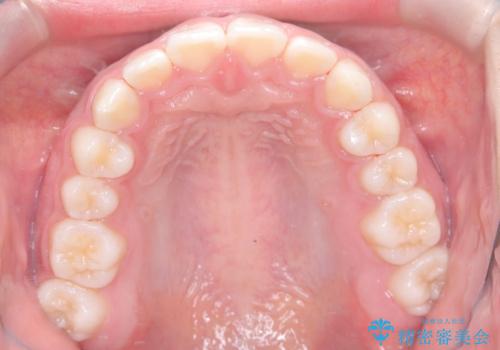

まず、上顎にリンガルアーチを装着し、歯列の幅を適正に維持しながら遠心移動をサポート。さらに、**TAD(矯正用アンカースクリュー)**を利用することで、奥歯を固定源とせずに前歯だけを後方へ移動させることが可能になりました。これにより、抜歯をせずに前歯の突出を抑え、バランスの取れた口元へと改善。治療後、患者様からは「抜歯せずに理想の仕上がりになり、大満足」とのお声をいただきました。